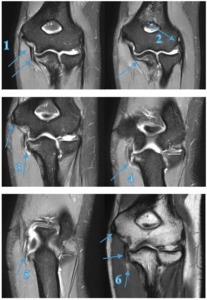

Athlete A

A 21-year-old elite male Javelin thrower (Australian representative) presented with right sided medial elbow pain, rating up to 8/10 (NRS), with a history of right medial elbow issues including medial epicondylitis and FCU tendinosis. The physical examination findings were primarily palpatory tenderness at the UCL over the joint line (oblique ligament location) and at the sublime tubercle attachment, positive orthopaedic tests for the shoulder and elbow, with changes in the elbow extension (160°), shoulder flexion (150°) and abduction (160°) and internal rotation (IR) (55°) (Table 2). The athlete only experienced pain in posterior medial elbow when throwing at high intensity or when in full elbow flexion during the catch phase of an Olympic clean exercise. Because the athlete was unable to compete at an elite level seven weeks post symptom onset, he was referred for a magnetic resonance imaging (MRI) scan of the right elbow, which revealed a high grade UCL tear with a small associated avulsion fracture with no ligament displacement (Figure 2). Subsequent consultation with an elbow orthopaedic specialist recommended surgery on the ligament however athlete, coach and chiropractor all agreed to attempt conservative therapy.

A 17-year-old amateur male Javelin thrower (State Representative) presented with right elbow pain which occurred during a competition 4 days prior. He described an audible pop and sharp pain experienced just before releasing the javelin. In the six weeks prior to the competition, the athlete experienced minor discomfort 3/10 (NRS) in the shoulder and medial elbow, which would ease at the completion of training and competition. As presented in Table 2 the physical examination findings, there was obvious swelling and palpatory tenderness over the medial elbow joint line (UCL/FCU & FDS tendons) and the medial epicondyle. The medial elbow dysfunction was exacerbated by any gripping or pronation motion reporting an 8/10 (NRS) at worst, reducing to 4/10 with the influence of ice, anti-inflammatories and analgesics as presented in Table 2 and 3. All activities ceased immediately until the pain and swelling was reduced. Due to the mechanism of injury and clinical findings, the practitioner referred him for MRI (Figure 3) which revealed a full thickness tear to the anterior bundle of the UCL with a low-grade partial tear of the FCU muscle, distal to the common flexor origin, which dictated the treatment choices and future modification to the training program.

The initial phase of Athlete A’s treatment and rehabilitation schedule was initiated with training modifications based on symptoms, with the goal of competing at week 6, as outlined in Appendix A and Appendix B. This was unsuccessful resulting in a complete remodel of the treatment and training program based off further investigation (MRI - Figure 2) and surgical opinion. After altering the treatment (Appendix A), rehabilitation, and training (Appendix B) over a 15-week period, the athlete rated “Excellent”37 Conway Scale (Table 3) and returned to high level competition at week 24 with a throw of 99.46% of previous personal best (PB) 76.34m (800g) and at week 27 a throw of 78.75m (800g) 3% greater than the previous PB.

Imaging

MRI has typically been the gold standard imaging modality in identifying tendon and ligament pathology such as UCL injuries, particularly when full-thickness tears are present.10,51,52 Athlete A’s UCL injury was diagnosed by physical examination and confirmed by MRI (Figure 2), and Athlete D (Figure 3) also had diagnoses confirmed by MRI.

The sports chiropractors decided not to refer Athlete B for imaging, rather using their clinical experience, the athlete’s history and clinical presentation to make a working diagnosis of pathological findings and initial conservative management. Athlete E was referred for x-ray (Figure 4) 5 days post injury incident to confirm a fracture to the medial epicondyle (Little Leaguers Elbow), after clinical examination suggested its likeliness.

The treatment and management was not dictated solely on these imaging findings, but in conjunction with the physical examination and clinic history.

Trauma resulting in valgus stress on the elbow, seen with athletes involved in throwing sports, are particularly susceptible to avulsion and stress fractures to the medial epicondyle or sublime tubercle due to the high load and forces during the acceleration and deceleration phase of the throwing action.53,60 Athlete A, was diagnosed a UCL tear/rupture and avulsion fracture of the sublime tubercle, confirmed on MRI. The tensile strength of the UCL is often overcome by the throwing force, especially in the elite athletes, where repetitive microtrauma can weaken and ultimately tear the ligament or cause avulsions fractures.61